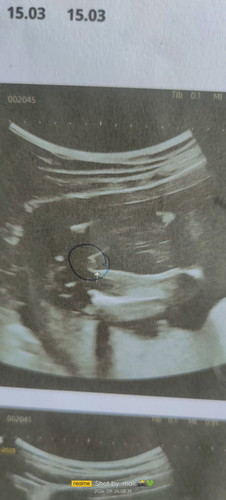

แม่ๆว่า ญ หรือ ช ค่ะ

อายุครรภ์ 18+5 ค่ะ หมอบอกว่า ญ 90%